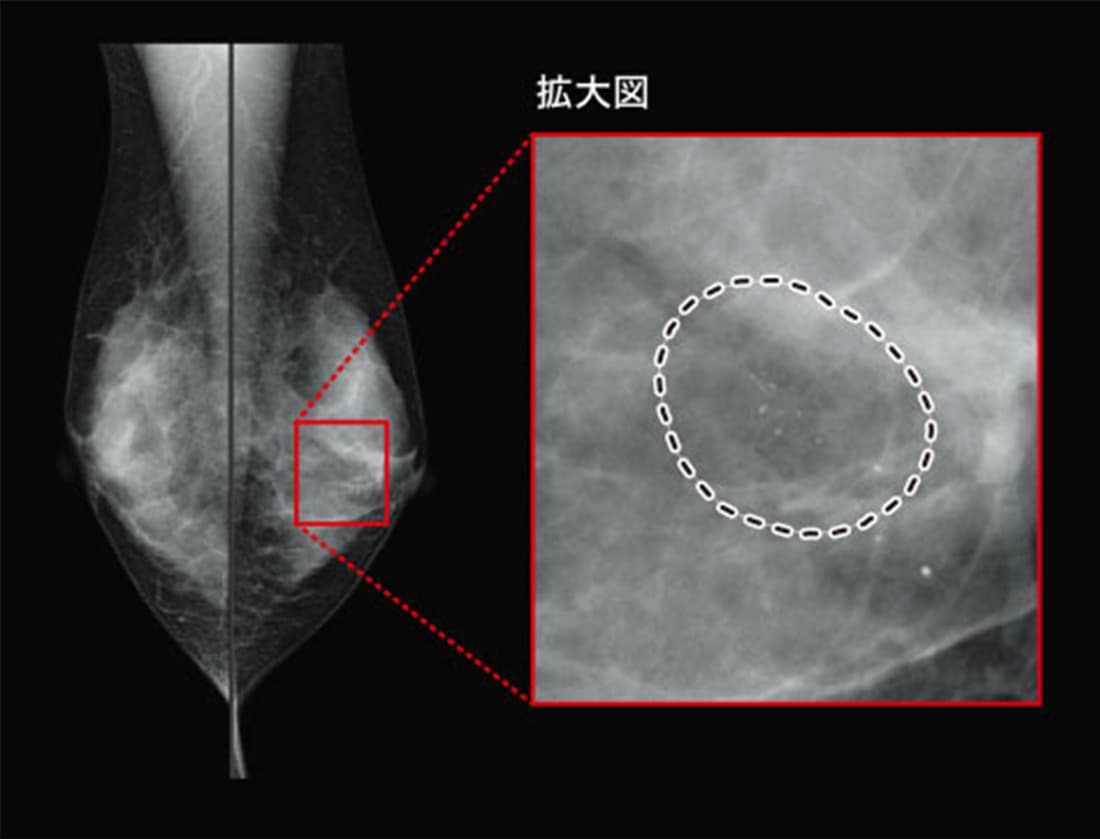

【症例1】 淡く不明瞭な微小石灰化クラスタ

CADは、症例1のような非常に淡い石灰化も検出します。以前は必ず最初にCADなしで読影していましたが、今は先にCAD結果を見て「このケースは石灰化があるか」を認識しながら進めるという使い方もします。